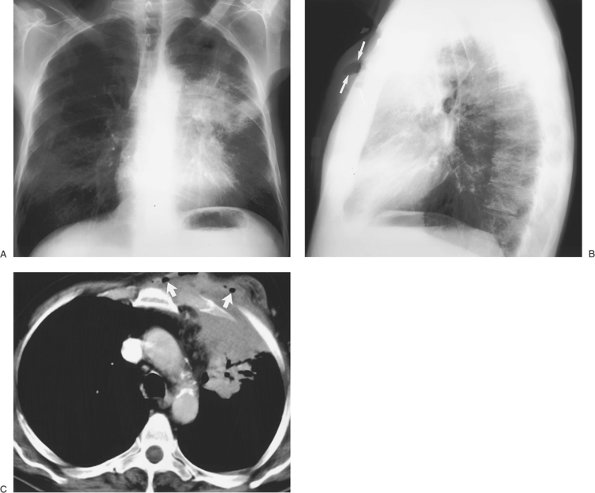

FIGURE 9-4. Pancoast tumor. PA (A) and lateral (B) chest radiographs of a 61-year-old man with right shoulder pain and a 40–pack-year history of cigarette smoking shows a circumscribed mass (arrow) in the right apex. C: CT with bone windowing shows the mass filling the right lung apex and destruction of the right second rib (arrow).